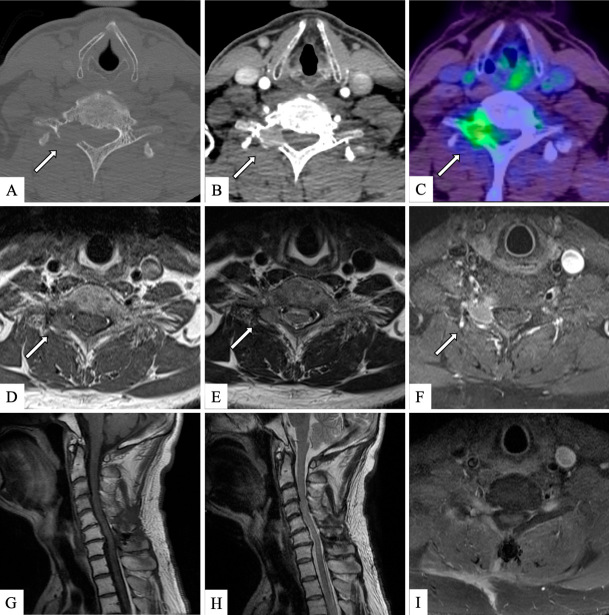

Surgical Treatment for Cervical Lamina Metastasis from Parathyroid Carcinoma: A Case Report.

甲状旁腺癌颈薄层转移的手术治疗:病例报告